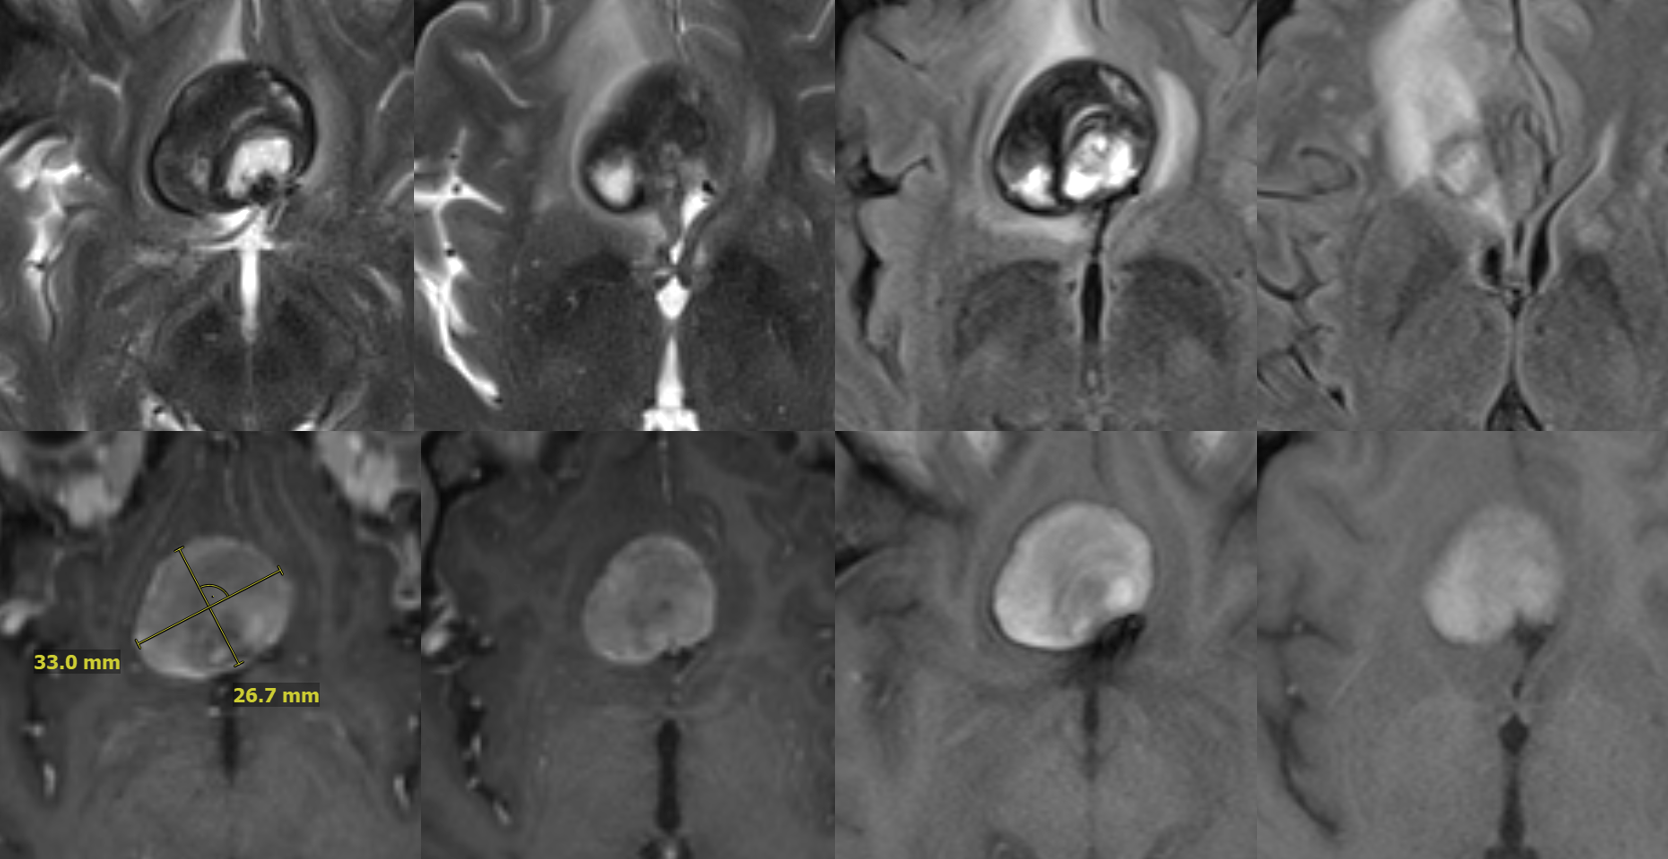

One month later — only 1 mo. Aneurysm thrombosed. Right A1-A2 patent — can tell on MRA even with two SVBs

Several months later, MRI looks fantastic — no edema, smaller, etc. This MRI is actually enough to know the aneurysm is gone. Its more sure than angio.

MRA